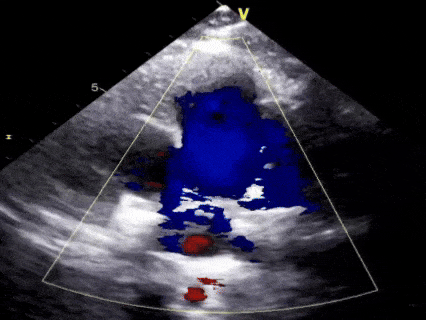

术后6个月随访

无残余分流,封堵效果良好

本病例为一例9岁患儿,超声心动图检查显示为典型的漏斗型PDA,肺动脉侧内径4mm,主动脉侧内径7mm;鉴于患儿处于重要生长发育阶段,术中选择全降解封堵器联合纯超声引导的治疗方案,选用经股动脉途径进行介入封堵,既通过可降解材料避免金属永久存留,又完全规避X线辐射风险。本例手术经股动脉路径植入全降解封堵器(腰高5mm、腰部直径9mm),严格遵循“一贴二扣三锁四剪五撤”的5S规范化操作,超声影像清晰地观察到封堵器的释放过程及其与PDA的贴合情况,术后即刻评估显示封堵效果理想,无任何残余分流。术后3个月及6个月随访均无残余分流,封堵效果良好。